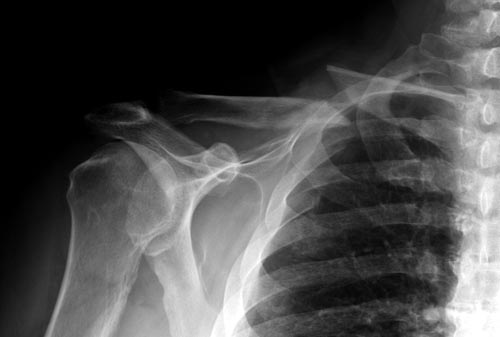

Болезненные ложные суставы надо оперировать, и здесь представлен случай

свежего болезненного ложного сустава, оперированного через 4 месяца.

Освобожден средний фрагмент и боковая компрессия лагированием, фиксация

пластиной..

Вложение не в текстовом формате было извлечено…

Имя     : Clavicle 4 one month.jpg

Тип     : image/jpeg

Размер  : 26336 байтов

Описание: отсутствует

Url     : http://weborto.net:8080/pipermail/ortho/attachments/20141124/0ee515fb/attachment-0036.jpg